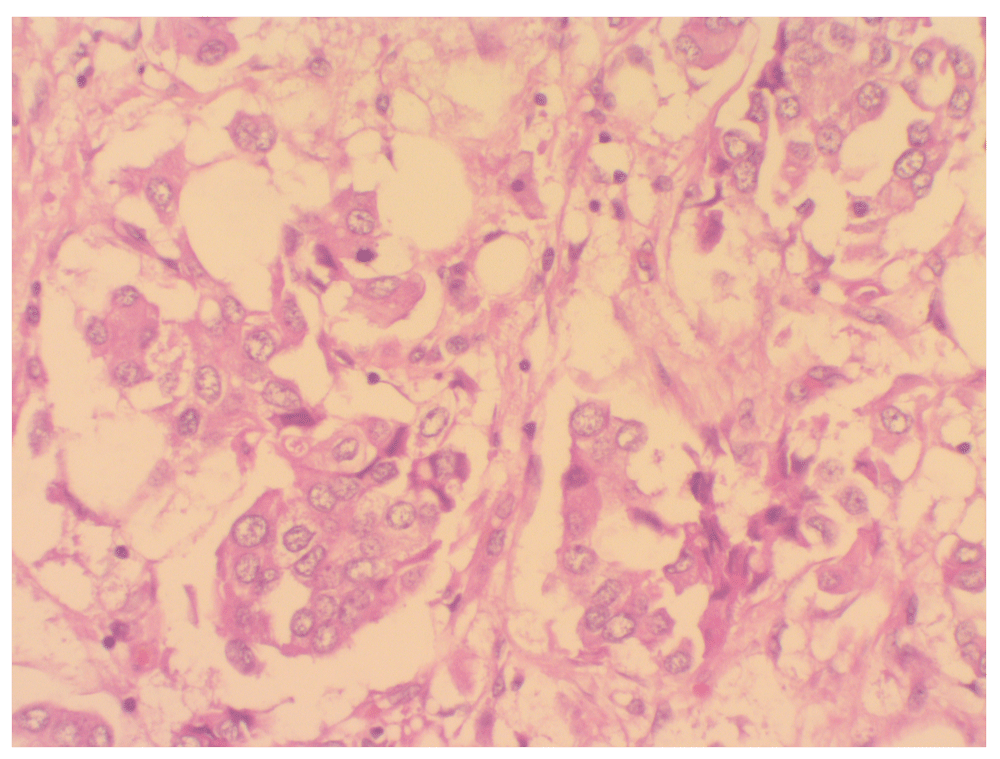

Left breast and axillary dissection histopathology assessment (April 2017). On macroscopic examination the left breast nipple and skin were unremarkable. On section a tumour was noted in the lower outer and inner quadrants. It measured 40mm in maximal diameter. Microscopically, the tumour comprised infiltrating epithelioid cells in a nested growth pattern, with some tubule formation. There was marked nuclear pleomorphism, and eight mitotic figures were noted in ten high power fields. The modified Bloom and Richardson classification was Grade 2. Five lymph nodes were identified, and all of these contained tumour metastases.

Immunohistochemical stains were positive for estrogen receptors, negative for progesterone receptors, and equivocal for HER2. FISH testing was negative for HER2 amplification. Ki67 staining showed a proliferation index of 20% (Figure 1). The PSA immunochemistry staining was negative confirming primary breast carcinoma.

(H&E stain, X400 magnification).